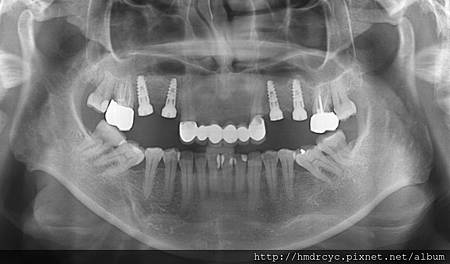

左營的T小姐有相同問題想做植牙

但上顎竇的骨頭不夠 直接做植牙會上顎竇穿孔

欣美牙醫植牙同時補骨用上顎竇增高術來保護上顎竇的完整

左營T小姐滿意的帶家人來回診

了解植牙同時補骨用上顎竇增高術來保護上顎竇的完整

評估後決定植牙同時補骨

用上顎竇增高術來保護上顎竇的完整

植牙後骨頭因為補骨而變厚

整個植牙體都被骨頭包覆 沒有穿進上顎竇